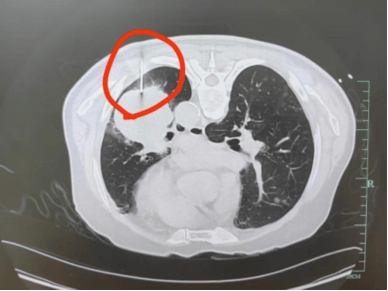

71岁的章爷爷咳嗽胸痛了半个月,儿女赶紧带他去浙大一院普胸外科检查,结果让全家揪紧了心:左肺有个4cm的肿瘤,考虑是中晚期,直接手术可能效果不佳,需要先行药物治疗控制肿瘤发展。但要制定治疗方案,必须先取到肿瘤组织、明确是哪种类型——这就离不开穿刺活检。

“这么大年纪,还能做穿刺吗?”家属的担心不是没道理。更棘手的是,章爷爷的肿瘤紧紧“贴”着心脏和大血管,稍微偏一点就可能引发大出血,危及生命。

胸外科医生立刻组织肿瘤科、放射科医生一起商量,最终定下了“CT引导下穿刺”的活检方案:

1.穿刺医生盯着CT屏幕,精准规划进针路线,避开心脏和大血管;

2.穿刺时跟着章爷爷的呼吸节奏“找时机”——吸气时肺会膨胀,呼气时稍微收缩,医生就趁章爷爷屏气的“间隙”轻轻进针;

3.只用了一根细针,就从肿瘤里取到了足够的组织,全程不到20分钟。

术后章爷爷没有出现气胸、出血等并发症,病理结果显示是肺鳞癌,浙大一院的医生很快就制定了针对性的方案,现在他的咳嗽胸痛症状已经减轻了不少。